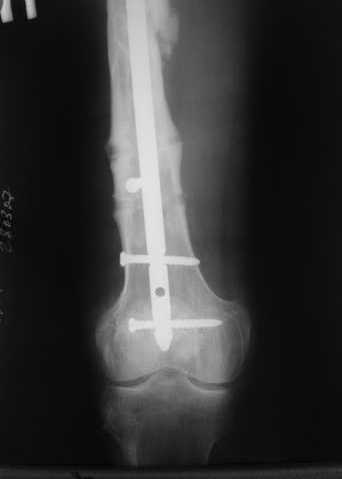

В приложении пример, как их использовали после остеотомии бедра по поводу сросшегося с вальгусом перелома, чтобы не дать гвоздю уйти во внутренний мыщелок.

Да, действительно красивый клинический пример: виден вальгус до операции и последующая коррекция углового смещения на "полярах". Я так понимаю, что в вашей клинике есть возможность использовать различные фиксаторы. Почему не использовали DFN? Спицы какие используете? Киршнера или Илизаровские? С виду очень тонкие...

В приложении пример, дистальный отломок пружинил кзади. Два винта потому, что первый оказался чуть кпереди и не упирался в гвоздь.